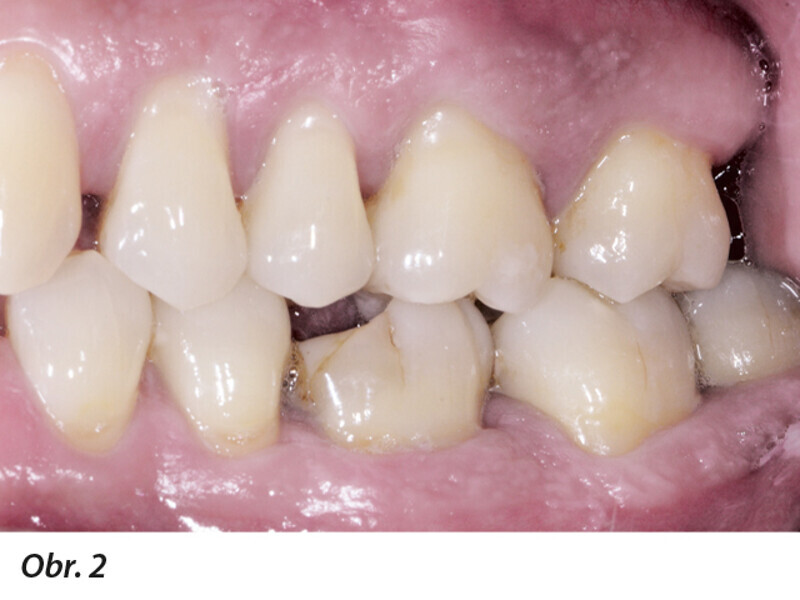

Multidisciplinární léčba u pacienta se závažnou parodontitidou